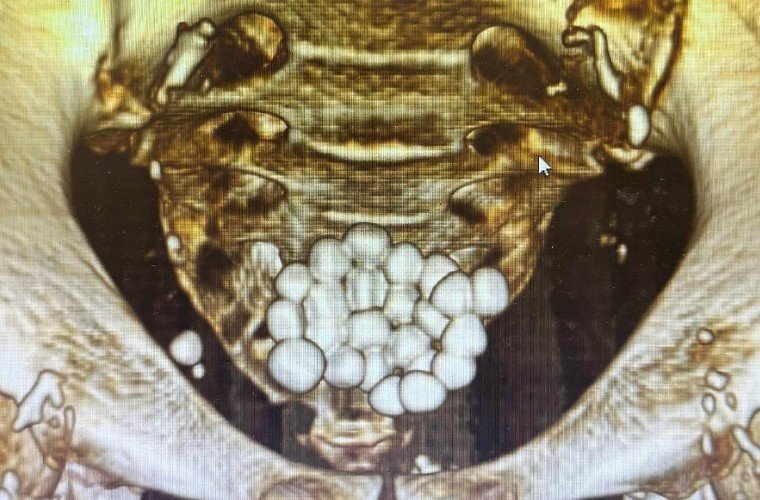

Новороссийске хирурги удалили 24 камня из мочевого пузыря пациента

Врачи горбольницы Новороссийска провели одновременно две лапароскопических операции одному пациенту. Они удалили 24 камня из мочевого пузыря.

На хирургический стол попал мужчина, страдающий аденомой простаты. Из-за осложнений у него образовалось два десятка камней диаметром до 1,5 см. Об этом «Кубань Информ» рассказали в пресс-службе медицинского учреждения.

Операцию провели врачи урологического отделения горбольницы: заведующий урологическим отделением Игорь Довлад и лечащий врач Арслан Темиров. Они одномоментно удалили все камни из мочевого пузыря и провели трансуретральную резекцию простаты.

Операция прошла без разрезов — с помощью современного эндоскопического оборудования. Сейчас пациент чувствует себя хорошо. Через несколько дней его выпишут домой без медицинских трубок. Медики напомнили, о коварстве заболевания, оно протекает безболезненно и проявляется у мужчин старше 45 летнего возраста.